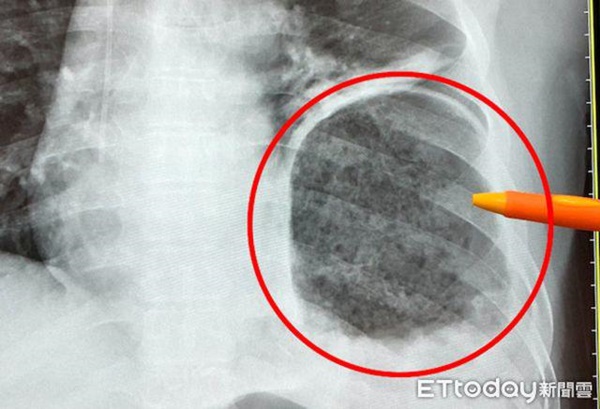

Phim chụp phổi của ông Lý bị dạ dày chèn ép, cơ hoành bị vỡ

Bắc sĩ Ngô Chính Nguyên, Trưởng Khoa phẫu thuật lồng ngực của Bệnh viện Từ Tế Đài Trung cho biết, khi đó ông Lý quay lại phòng khám, bác sĩ Khoa đại trực tràng phát hiện có điều không ổn, vội vàng chuyển ông Lý đến khoa Phẫu thuật lồng ngực, sau khi kiểm tra chụp cắt lớp CT mới phát hiện ra vấn đề này. Hình ảnh chụp cắt lớp cho thấy dạ dày bị sưng và đầy thức ăn, phối bên trái bị dạ dày ép một nửa, may mắn thay, phổi không có vì bị ép mà dẫn đến khó thở, nhưng nếu phổi lại bị kéo xuống, có thể dẫn đến xoắn dạ dày, hoại tử do thiếu máu, nghiêm trọng hơn là mất mạng.